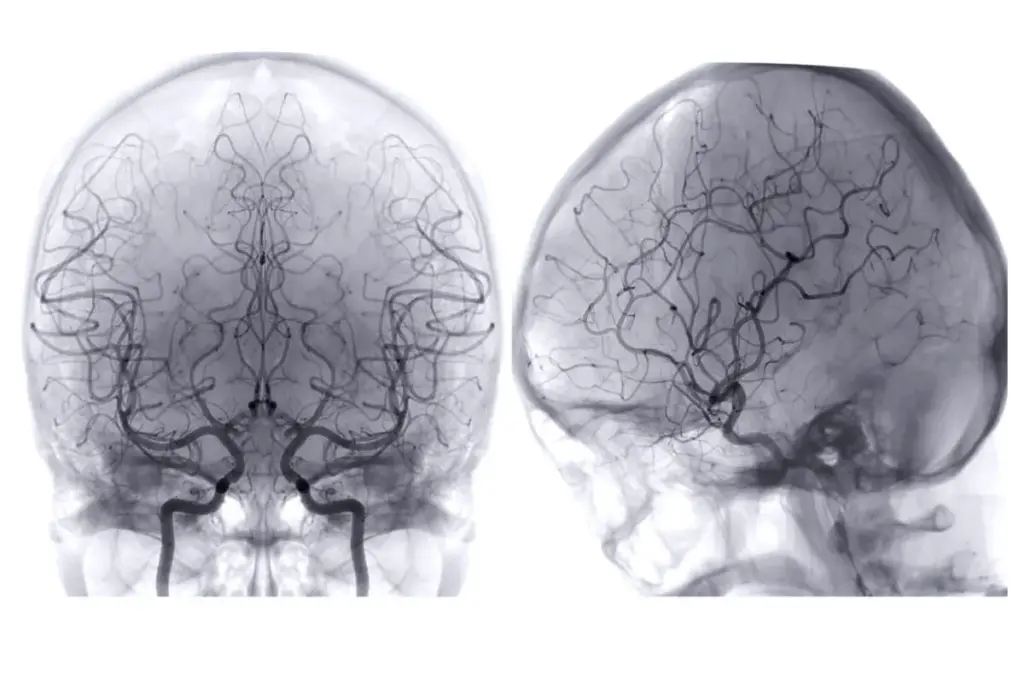

SEP 6711 image 2 LIV Hospital

Fluoroscopy is a medical imaging method that shows real-time X-ray images. It helps doctors diagnose and treat many health issues. This technology lets them see how internal parts move, which is key in interventional radiology.

Fluoroscopy uses a fluoroscope, which has an X-ray source and a fluorescent screen. X-rays pass through the body, showing different images on the screen. This helps doctors place instruments or contrast agents accurately.